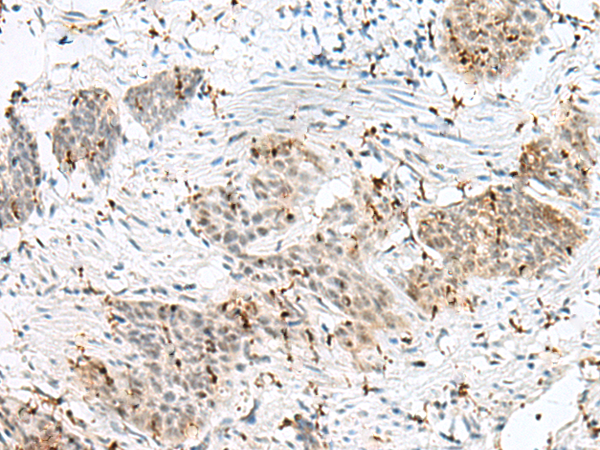

分类: 科研抗体货号: P09960别名: PC5; PC6; PC6A; SPC6应用: IHC反应种属: Human, Mouse, Rat